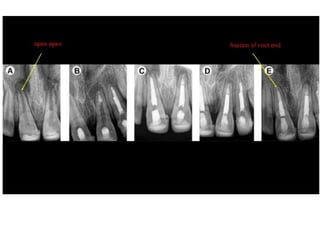

APEXOGENESIS AND

APEXIFICATION

Root Apex

BLUNDERBUSS

CANAL???

• It is defined as a method to induce

development of the root apex of an

immature pulpless tooth by

formation of osteocementum/ bone

like tissue

-cohen

• Apexification is a method of

inducing apical closure through the

formation of mineralized tissue in

the apical pulp region of a non-vital

tooth with an incompletetly formed

root and an open apex

-morse etal 1990